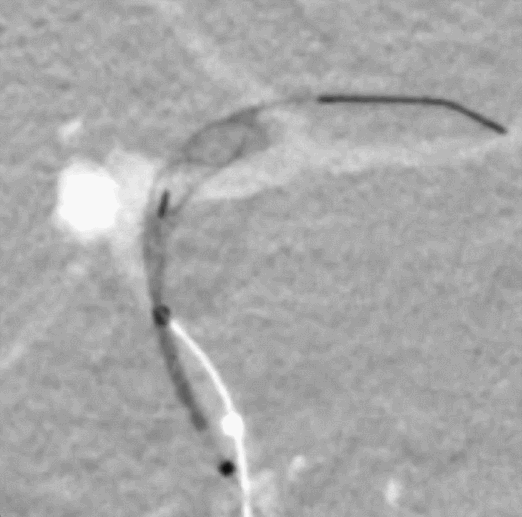

Tubridge Plus Case 3